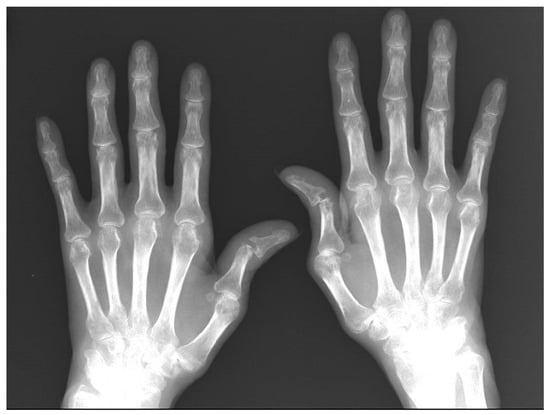

- Case 3. Felty Syndrome. The patient is a 46-year-old woman with RA according to EULAR/ACR criteria [7], with poor prognostic characteristics (high levels of activity, RF+, ACPA+, erosions and poor physical function) as evaluated in 2011, with poor compliance. From 2011 to 2015, she received irregular treatment with methotrexate, leflunomide, and low doses of oral prednisone and refused bDMARDs. In 2019, she returned to the clinic with six swollen joints, eight tender joints, 6 cm of visual analogue scale of pain (0 = no pain to 10 = maximum pain), and 6 cm of VAS of RA activity (0 = no activity to 10 = maximum activity), with DAS28PCR 5.07, HAQ 1.5 and poor perception of health. We found hand deformity with ulnar burst and swan neck fingers (Figure 1).